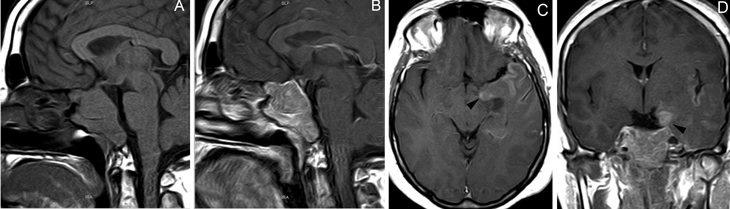

Figura 2A y B. Cortes sagitales de RM y TAC. Adenoma pituitario con invasión del esfenoides y del clivus (puntas de flecha). Es posible demostrar las estructuras óseas en RM con similar precisión que la TAC.

Figura 12A. Microadenoma pituitario (8 mm), corte coronal, secuencia convencional T1w con Gadolinio, el tumor lateralizado a derecha, erosiona y deforma el piso de la silla turca (punta de flecha). B. Mismo paciente, 3 meses post-tratamiento médico, corte coronal secuencia T1w con Gadolinio, El tumor ha modificado su forma, se ha reducido de tamaño (punta de flecha) y la glándula muestra ahora un borde superior cóncavo, con una pequeña herniación de la cisterna supraselar. Los macroadenomas pituitarios producen expansión de la silla turca, con moderado refuerzo del tumor después de la inyección de gadolinio. La densidad (TAC), intensidad de señal (RM) y características del refuerzo con medio de contraste yodado (TAC) o gadolinio (RM) no son específicas, pero el aumento de volumen y erosión de la silla turca, la invasión del seno cavernoso y la presencia de contornos lobulados (64%) son hallazgos frecuentes en un macroadenoma42-44. El aumento de volumen selar se observa en 94 a 100% y la erosión de las paredes de la silla turca, incluyendo el piso selar, dorso selar, tubérculo selar y extensión al seno esfenoidal, está presente en 76% de los macroadenomas. La invasión del hueso esfenoides y del clivus (Figura 2Ay 2B) se demuestra en 19% de los casos.